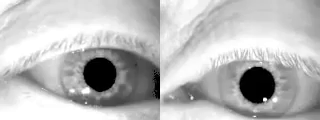

Animated GIFнистагм GIFнистагм GIF